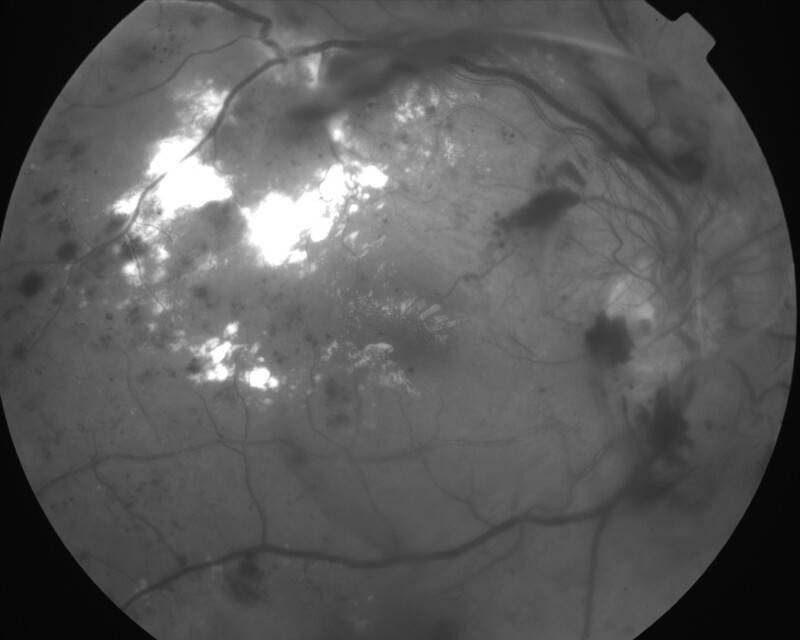

RETINOPATHIE DIABETIQUE PROLIFERANTE

IMG0001.JPG